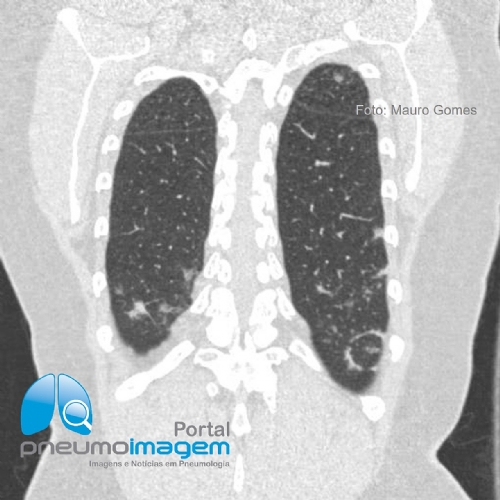

CASO CLÍNICO #62

Qual o nome desse sinal tomográfico e em qual doença ele foi descrito? Deixe seus comentários abaixo.

What is the name of this tomographic sign and in what disease was it described? Write your comments below.